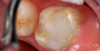

The repaired molar is shown immediately after treatment (Figure 4) and at 13 months (Figure 5). It was hoped that the restoration of the molar would last long enough that stainless steel crown full coverage would not be needed before precision cast crown placement late in the teen or adult years. However, stainless steel crown coverage could be considered, as needed, pending more eruption of the tooth.

Images of the repaired molar immediately after restoration

Figure 4

13 months postoperatively

Figure 5